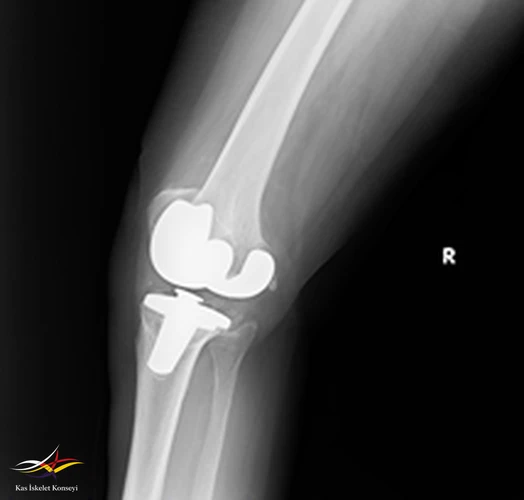

Hikaye: Dört yıl önce sağ dize total protezi uygulanan hastanın üç ay önce ortopedi kliniğine aynı dizde ağrı ve eklemde kısıtlılık ile başvurduğu ve mevcut protezin revize edilmesi kararı verildiği öğrenildi. Başvurmasından iki ay önce revizyon diz protezi yapılıyor. Ameliyattan sonra düşük ayak gelişiyor. Ev egzersizleri, ortez ve multivitamin ile taburcu ediliyor.

Özgeçmiş: 4 yıl sağ diz protezi, HT.